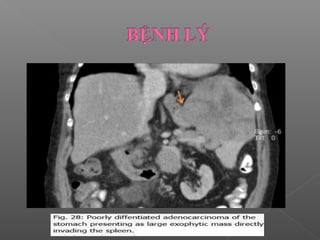

 Ung thư dạ dày

Ung thư phổ biết nhất là ung thư biểu mô tuyến

 Ung thư biểu mô tuyến

Phổ biến nhất, hay gặp là ung thư tuyến nhầy.

CT: khối có bờ không đều hoặc thành dạ dày dày lan

tỏa không đều

 Ung thưbiểu mô tuyến Phổ biến nhất, hay gặp là ung thư tuyến nhầy. CT: khối có bờ không đều hoặc thành dạ dày dày lan tỏa không đều